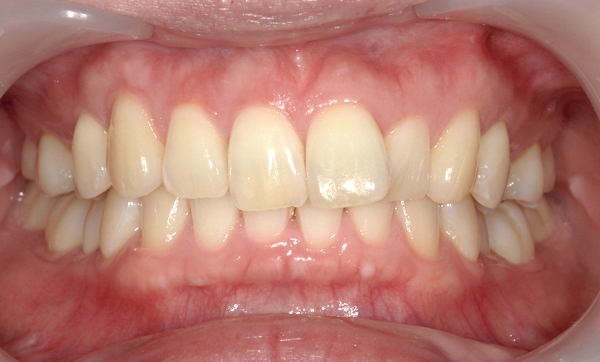

症例_001 「出っ歯」症例

治療期間:13ヶ月金額:54万円+税20代女性出っ歯捻転歯

| Before | After |

|---|---|

|